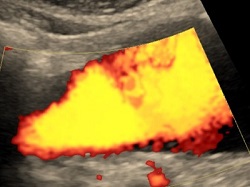

Doppler aorty i tętnic biodrowych lub trzewnych

Badanie wykonywane w celu oceny tętniaków i zwężeń w tętnicach brzucha. Do badania trzeba być około 4-6 godz. na czczo i przyjmować 1 dzień wcześniej Espumisan.

Tętniak aorty brzusznej.